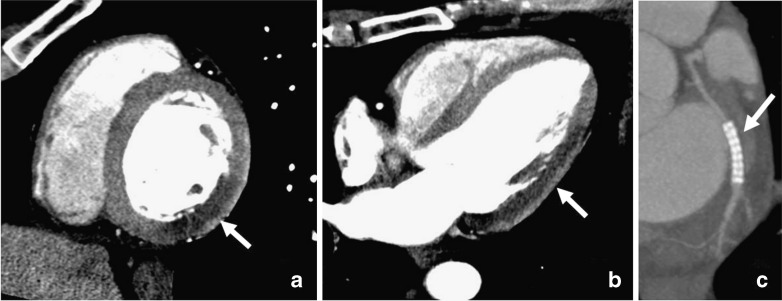

Fig. 2.

CTCA demonstrating a non-calcified (a), a mixed (b), and a calcified (c) coronary arterial plaque

With 64-slice CT, a sensitivity of 83% was found for detecting non-calcified coronary artery plaques. Regarding calcified plaques, a higher sensitivity of 95% was demonstrated [18]. Comparable results were reported by other groups employing 64-slice CT [15], indicating a still suboptimal spatial and temporal as well as contrast resolution of CT. Importantly, observer experience also has a significant impact on the accuracy of plaque detection [19].

Regarding the quantification of coronary arterial plaque volume with CT, correlations are only moderate compared with IVUS. In general, the accuracy varies with coronary arterial plaque composition: volumes of non-calcified and often also mixed plaques are frequently underestimated, whereas the volume of calcified plaque is often overestimated in CT [20]. The latter can be explained by blooming artefacts and by partial volume effects caused by the contrast-enhanced vessel lumen. Finally, standardised and software-based automated assessment of coronary plaques with CT is still lacking [21]. Quantitative coronary artery plaque composition has been repetitively assessed with various CT generations [22, 23]. Most investigators measured CT numbers (in Hounsfield units) to determine the ability of CT to characterise and to distinguish the various plaque types. However, although early study results were promising, studies have consistently shown that CT numbers of non-calcified plaque components vary widely. Although mean values were often significantly different between fibrous and lipid-rich coronary arterial plaques, a substantial overlap of CT numbers was found, precluding a reliable characterisation and differentiation of the various non-calcified coronary arterial plaques [15]. Furthermore, measurements of CT numbers in coronary plaques should be made with caution, because contrast enhancement within the vessel lumen considerably affects attenuation measurements of the plaques in the adjacent vessel wall [24]. Also, the use of different tissue reconstruction filters affects the CT numbers of coronary arterial plaques [25].